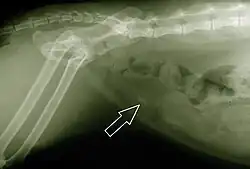

Diagnosis

When symptoms indicate bladder stones, the first step is usually to take an x-ray. Most types of stones will appear readily in an x-ray, urate and occasionally cystine stones being the most common exceptions. Stones smaller than three millimeters may not be visible.[4] Ultrasonography is also useful for identifying bladder stones. Crystals identified in a urinalysis may help identify the stones, but analysis of the stones is necessary for identification of the complete chemical composition.